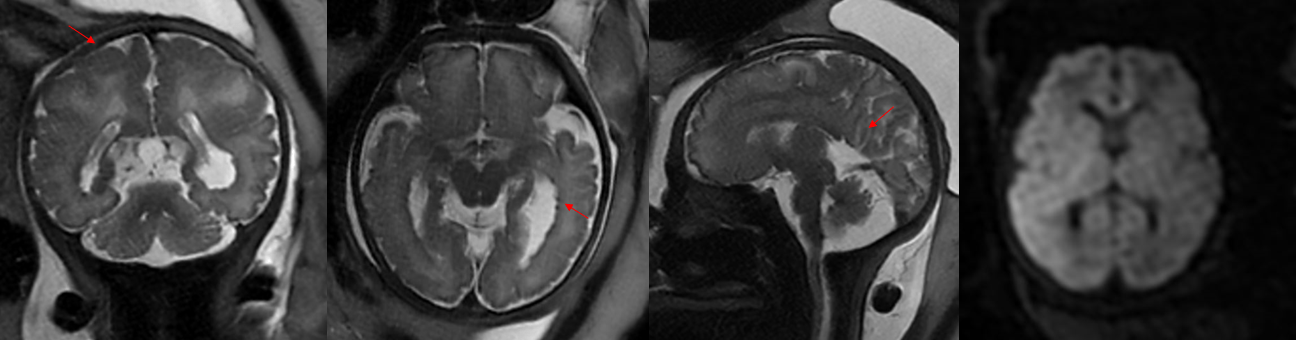

临床资料:孕36.1周;超声提示胎儿第三脑室后方囊性结构(蛛网膜囊肿待排)

影像诊断:双侧脑室边缘多发小结节影伴双侧额叶皮层增厚,脑回宽大,多考虑神经元移行障碍性疾病